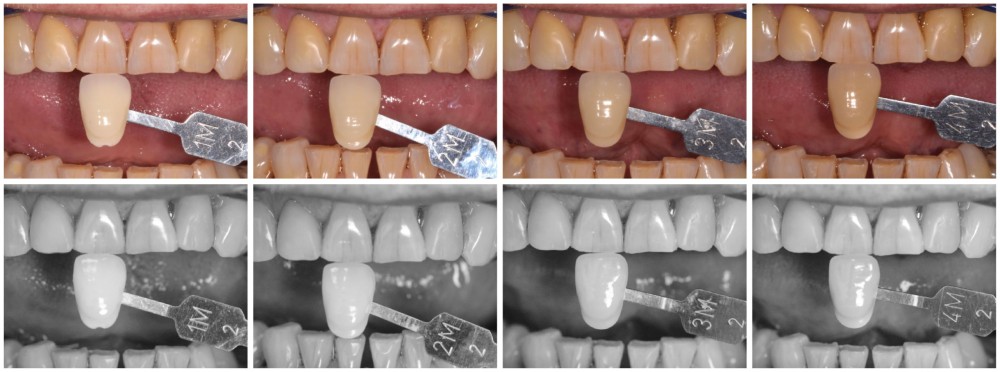

La proposition thérapeutique retenue par le patient est donc une réhabilitation par couronne céramique sur 12 (dento-portée) et 22 (implanto-portée). Ce choix thérapeutique impose de concevoir des dents qui s’intègrent au mieux dans l’harmonie du sourire, tout en étant conscient des limites d’un tel traitement.